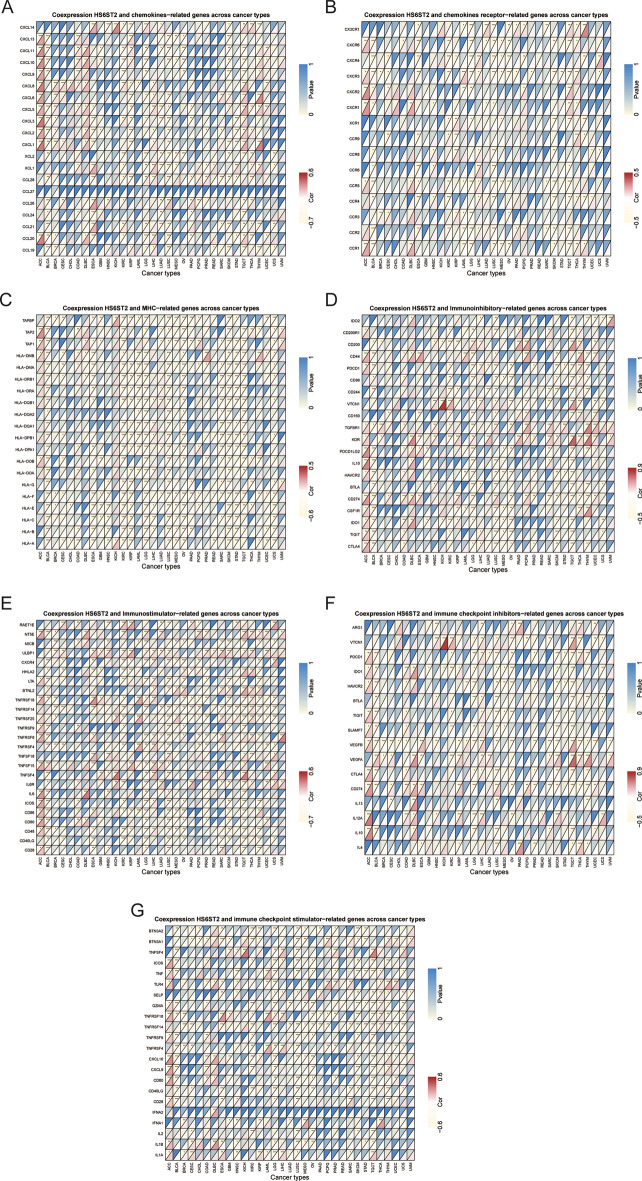

The connection between HS6ST2 and immune-related gene expression

Next, we used gene coexpression analysis to look for links between HS6ST2 expression and genes involved in the immune system in 33 different cancers. CXCL5, a gene linked to chemokines, was found to have a positive correlation with HS6ST2 expression in 16 tumor samples, showing a positive correlation in testicular germ cell tumors, breast invasive carcinoma, uterine corpus endometrial carcinoma, adrenocortical carcinoma, liver hepatocellular carcinoma, thymoma, colon adenocarcinoma, lymphoid neoplasm diffuse large b-cell lymphoma, and skin cutaneous melanoma but a negative correlation in bladder urothelial carcinoma, lung adenocarcinoma, kidney renal papillary cell carcinoma, thyroid carcinoma, lung squamous cell carcinoma, pancreatic adenocarcinoma, and esophageal carcinoma (Fig. 10A). As demonstrated in Fig. 10B,C, HS6ST2 expression was inversely correlated with CXCR3 and HLA-F in 13 malignancies (Supplementary Table S1). Additionally, we assessed the link between HS6ST2 and genes involved in immunological stimulation, immune suppression, and immune checkpoints. The findings showed a positive association between the expression of KDR and ULBP1 and HS6ST2 expression in 11 different types of cancer (in particular, kidney renal papillary cell carcinoma, sarcoma, skin cutaneous melanoma, thyroid carcinoma, and uterine corpus endometrial carcinoma) (Fig. 10D,E). On the contrary, the expression levels of VEGFB and TNFRSF14 were negatively correlated with HS6ST2 in breast invasive carcinoma, cervical squamous cell carcinoma and endocervical adenocarcinoma, lung squamous cell carcinoma, brain lower grade glioma, ovarian serous cystadenocarcinoma, skin cutaneous melanoma, sarcoma, thymoma, and uterine corpus endometrial carcinoma (Fig. 10F,G). Our findings indicate that HS6ST2 may have a role in tumor progression and immune evasion through the regulation of immune-related genes.

According to our findings, HS6ST2 also plays a crucial role in cancer immunity. The TME is important for cancer progression and therapeutic response33. HS6ST2 expression was found to be inversely related to stromal and immune cell composition in the TME in LUSC, BLCA, and LGG, but not in THCA, as measured by ESTIMATE scores. Immune cells that invade tumors play an important role in maintaining stability within the TME and in the development and treatment of cancer36,37. The TME contains a large number of M2 macrophages, and naive B cells may provide support for tumor growth38,39. HS6ST2 had a positive relationship with the levels of M2 macrophages cells and naive B cells in many malignancies. Those findings may explain the function of HS6ST2 as a risk factor in the majority of tumor types. In addition, our research confirmed the coexpression of HS6ST2 with genes related to immunological function. The HS6ST2 expression level was significantly connected with immune-related genes involved in tumorigenesis but was negatively correlated with CXCR3 and HLA-F40,41. All of these findings suggest that modulating HS6ST2 expression may also be a viable method for improving immunotherapy outcomes.